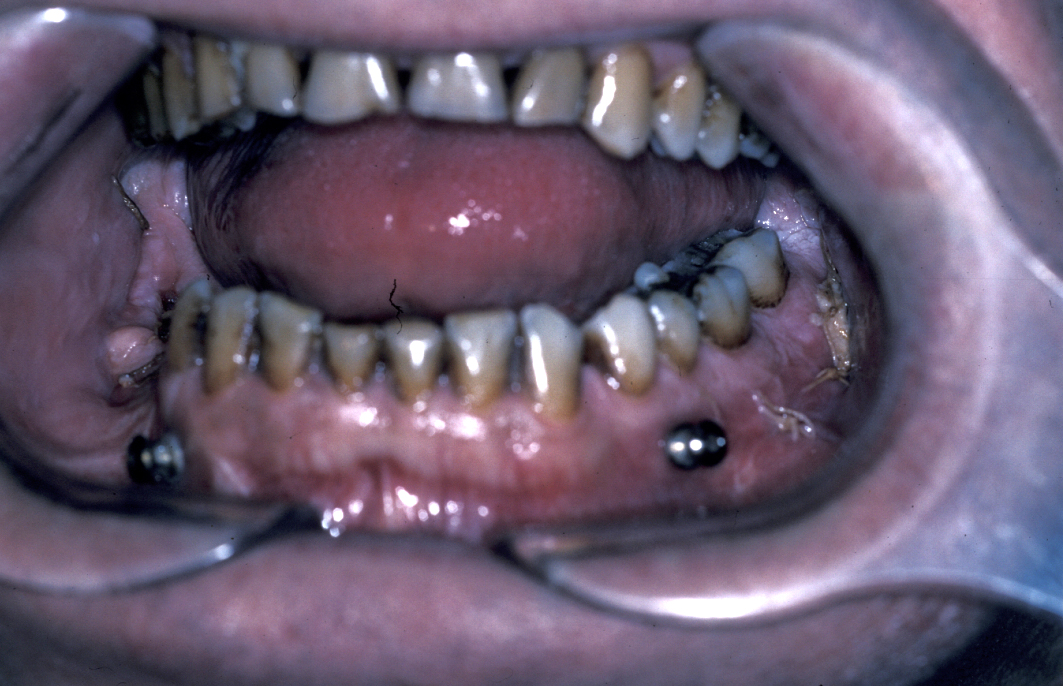

In the region of the angle of the mandible, a single plate is adequate to allow healing. In practice many surgeons now supplement this (or even replace it) with a transbuccally placed lateral plate which prevents lateral displacement of the lower border of the mandible. All these techniques use monocortically placed matching titanium screws to retain the plates which immobilise the fracture sites. Long-acting local anaesthetic regional block provides good postoperative analgesia and prophylactic broad-spectrum antibiotics are given preoperatively. Intraoral wounds are closed with resorbable sutures. If the occlusion is fully restored and stability of the fracture is assured by the plates, the intermaxillary fixation can be removed. Postoperative radiographs are taken to ensure correct placement of plates and screws and accurate realignment of mandibular fragments. It is also important to reassess the position of the condyles following ORIF as malpositioning can lead to TMJ problems later on (see Figure 5).